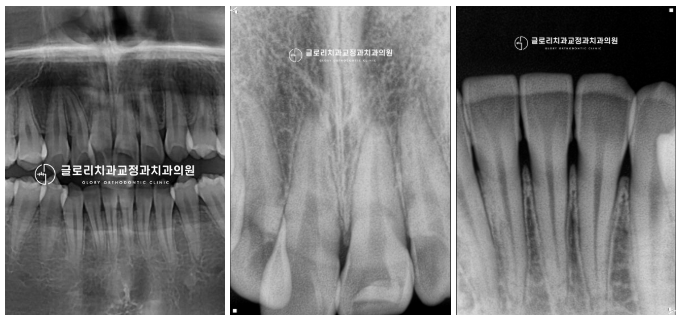

『3) 엑스레이』

치근의 길이 또한 문제가 없었으며,

맹출 장애도 발견되지 않았습니다.